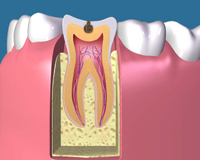

C1 虫歯の初期です。 ほとんど痛みがありませんので、麻酔をせず虫歯の部分を削 ってレジン製の詰め物(白いプラスティック)を入れて治療 は終わります。 |

C2 虫歯の中期です。虫歯の部分を削るのは前段階と同じですが、 削る量が大きくなります。 型をとり、詰め物を入れます。 レジン製の白い詰め物は使えない場合があります。 |

むし歯で歯に穴があくと、その進行の度合いによってC1、C2、C3、C4というように分類されます。

(Cとは、英語のむし歯の略称で、数字が大きくなるほどむし歯が進行していることを表します。)